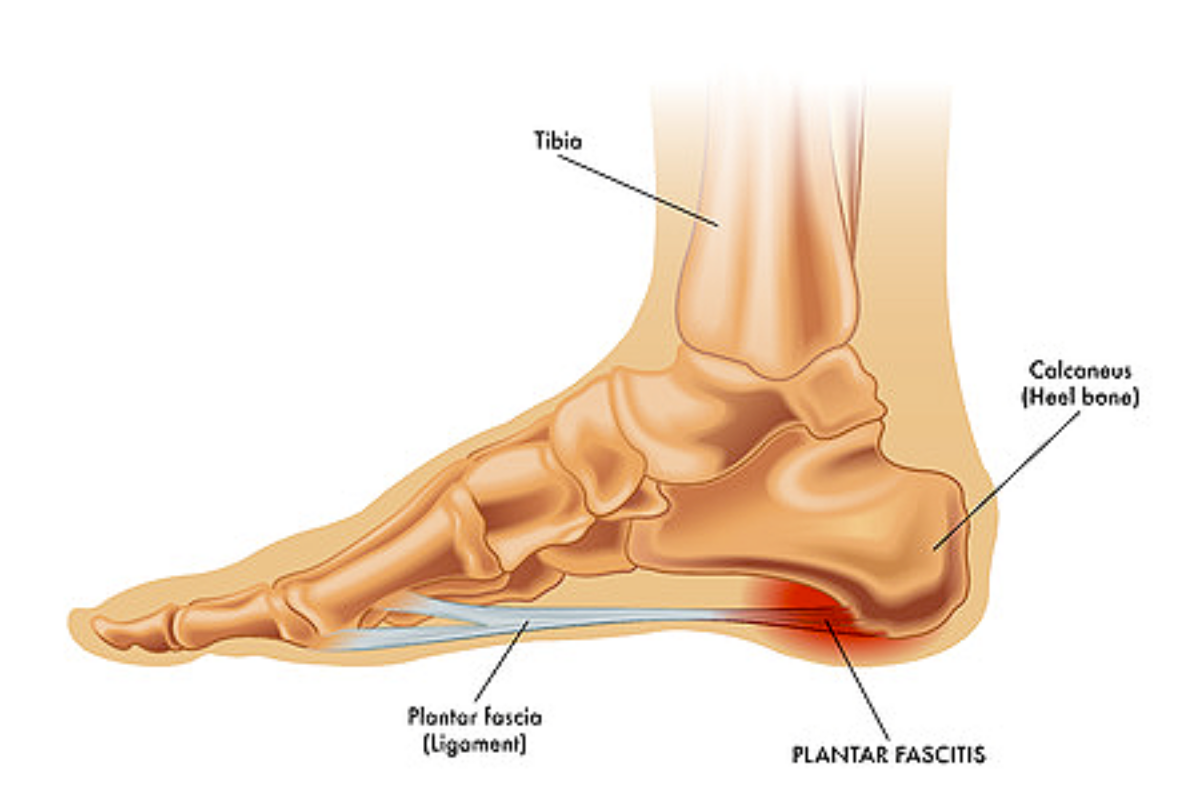

The more likely cause of heel pain is plantar fasciitis, the inflammation of a tissue called the plantar fascia which inserts into the bottom of the heel. Research confirms this with one study showing heel spurs to be a normal variant in the foot and only 3% of heel spurs being located within the plantar fascia, which could mean that it could damage the fascia and produce heel pain. Another study that looked at patients with heel pain in one foot showed that almost half of them had heel spurs in both feet, while 39% had no heel spurs in either foot. A few even had a heel spur in the opposite foot to the one they were experiencing their pain in.

Plantar fasciitis is one of the most common causes of heel pain. It involves inflammation of a thick band of tissue that runs across the bottom of each foot and connects the heel bone to the toes, known as the plantar fascia.

Plantar fasciitis commonly causes stabbing pain that often occurs with your first steps in the morning. As you get up and move, the pain normally decreases, but it might return after long periods of standing or when you stand up after sitting.